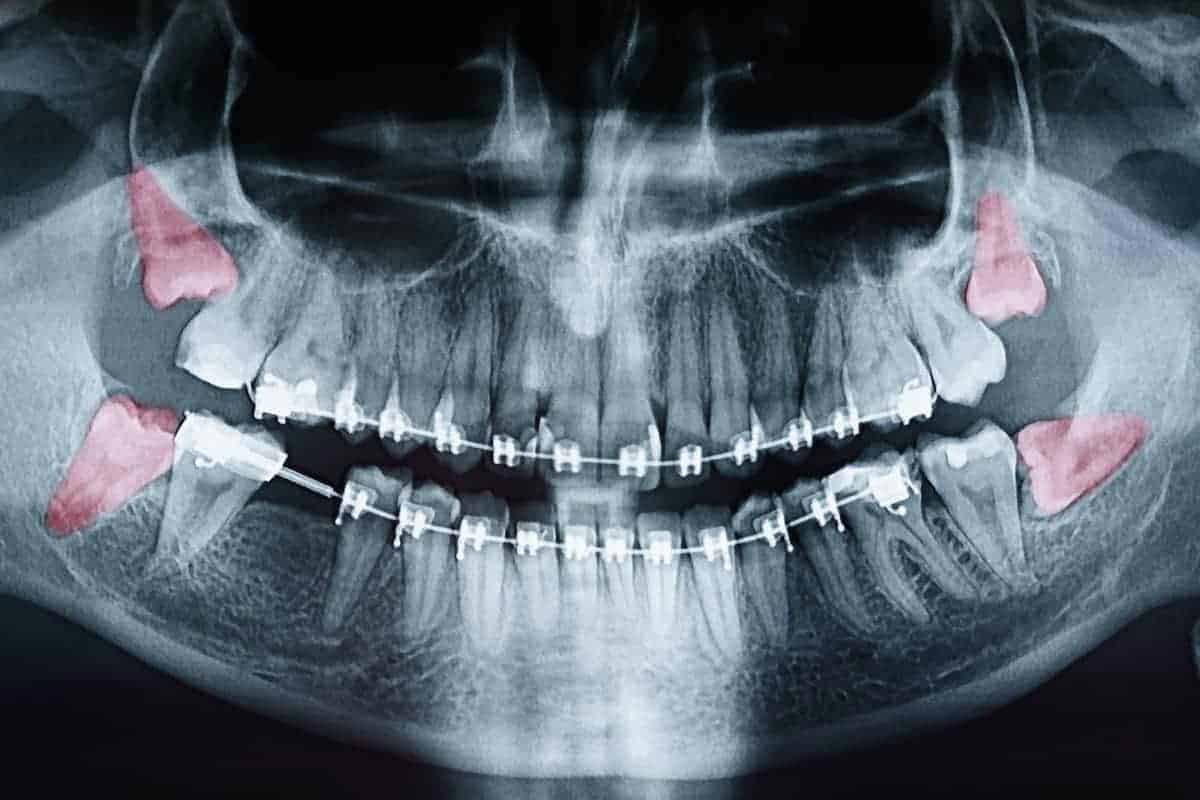

Most people’s mouths only have enough room for 28 teeth. When your wisdom teeth start to come in, that’s four additional teeth trying to cram their way in. In the majority of situations, this creates a litany of problems, including crowding, soreness, risk of infection, and the need for extraction. Since your wisdom teeth are the last teeth to erupt through your gums, they come to the party a little late. All your other teeth have settled into their places. With x-rays and inspections, we can determine if your wisdom teeth are impacted and need to be removed.

Though some patients may not require the removal of their wisdom teeth, most often, it’s needed to protect your overall oral health. Wisdom teeth can begin to grow in sideways, only partially erupt, or even get stuck beneath the gum and bone. Known as impacted teeth, those that get stuck may resort to shifting positions as they try to find a pathway for eruption. When wisdom teeth don’t erupt through the gumline properly, they can create severe problems for the patient, including:

To evaluate the state of your wisdom teeth, we’ll first do a thorough examination and take x-rays of your mouth. This will help us determine if your wisdom teeth pose a current or future threat to your oral health. Early detection of issues results in better outcomes for our patients, so we recommend the first evaluation be completed in a patient’s mid-teenage years.

An impacted tooth simply means it is “stuck” and cannot erupt into function. Patients frequently develop problems with impacted third molars, also known as wisdom teeth. These teeth get “stuck” in the back of the jaw and can develop painful infections among a host of other problems. Since there is rarely a functional need for wisdom teeth, they are usually extracted if they develop problems.

Normally, maxillary canines are the last “front” teeth to erupt into place. They usually come into place around age 12 and cause any space left between the upper front teeth to close tighter together. If a canine gets impacted, every effort is made to get it to erupt into its proper position in the dental arch. The techniques involved to aid eruption can be applied to any impacted tooth in the upper or lower jaw, but most commonly are applied to maxillary canine (upper eye) teeth. Sixty percent of these impacted eyeteeth are located on the palatal (roof of the mouth) side of the dental arch. The remaining impacted eye teeth are found in the middle of the supporting bone but stuck in an elevated position above the roots of the adjacent teeth or out to the facial side of the dental arch.

The older the patient, the more likely an impacted canine will not erupt by nature’s forces alone even if space is available for the tooth to fit in the dental arch. The American Association of Orthodontists recommends a panorex screening x-ray, along with a dental examination, be performed on all dental patients at around the age of seven years to count the teeth and determine if there are problems with eruption of adult teeth. It is important to determine whether all adult teeth are present or missing.

Are there extra teeth present or unusual growths that are blocking the eruption of the canine? Is there extreme crowding or too little space available causing an eruption problem with the canine? This exam is usually performed by your dentist or hygienist who will refer you to an orthodontist if a problem is identified.